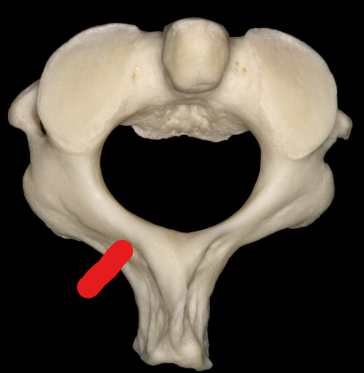

Atlas

Anterior tubercle

Anterior arch

Superior articular facet

Transverse foramen

Posterior arch

Posterior tubercle

Lateral masses